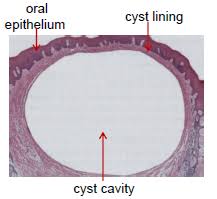

Cyst is defined as a pathological cavity may or may not be lined by epithelium and containing fluid , semi fluid or gaseous material .

The wall of the capsule is composed of the collagenous fibrous connective tissue usually within epithelial lining and it produces various bond reserving factors for its growth and expansion .

PARTS OF A CYST : Cyst has following parts: -> WALL (made of connective tissue) -> EPITHELIAL LINING. -> LUMEN OF CYST